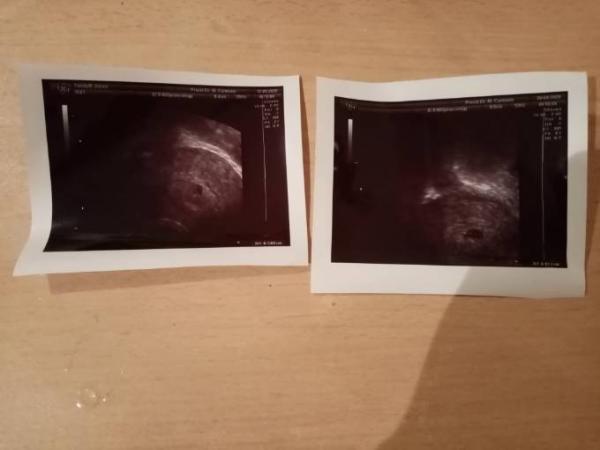

Sieht der FA am hcg wert ob mein baby im Bauch noch lebt? er hat mir jetzt gestern und heute blutabgenommen und morgen ist der Termin mit Dem Ergebnis ob es lebt oder ne Fehlgeburt ist sagt der Arzt ... Normal wäre morgen eine normale SS Kontrolle gewesen da das jetzt mit der Blutung dazwischen kam ach man es alles doof ...habe aber keine schmerzen oder so nichts :( :( hoffe alles geht gut !! Seht ihr an Hand der bilder einen unterschied also ich nicht es wächst aber diese Blutung :( aber bin ja auch erst 6ssw Doktor bluni oder bitte sagen sie mal was dazu bitte brauche endlich Klarheit das macht mich fertig :(

Hey. Ich kann auf den Ultraschallbildern noch keinen Embryo sehen, höchstens einen Dottersack. Aber das hat nichts zu heißen. Die Fruchthöhle sieht auf dem rechten Bild größer aus, als auf dem linken. Blutungen in der Schwangerschaft müssen auch nicht immer was schlechtes sein. Wenn der HCG Wert sinkt, ist das leider kein gutes Zeichen. Du wirst leider bis morgen abwarten müssen. Ich drücke dir die Daumen das alles gut geht

Okay danke ... Also erst war alles super aber da ich vor 2 Monaten eine AS in der 9ssw hatte hatte ich etwas Angst , als der FA dann am 16.4/sagte sie sind schwanger war ich über glücklich und hab mich rieseig gefreut er konnte mir da aber noch keine Woche nen da es noch zu früh war letzte Periode war ja am 26.3 und am 16.4 schwanger ....erste Termin verlief super alles war gut dann wäre morgen der normele Termin gewesen wie ich oben ja schon sagte :( da gestern aber Blutungen kamen bin ich sofort Zum Arzt er sagte hakt nur alles noch da wächst auch aber die Fruchtblase sieht wohl konisch aus ka was er damit meinte er sagte nur im schlimmsten Fall konnte es WD. Ne Fehlgeburt sein muss aber nicht :( :( er wollte dann 2 Tage blutabnehmen und den wert nach gucken und morgen entscheidet er !! Ja das eine Bild is etwas mehr ran geholt damit er das besser sehen kann aber ich fragte sofort is es größer geworden er sagte ja es geht nur um für Fruchtblase und wegen dem Blut ..